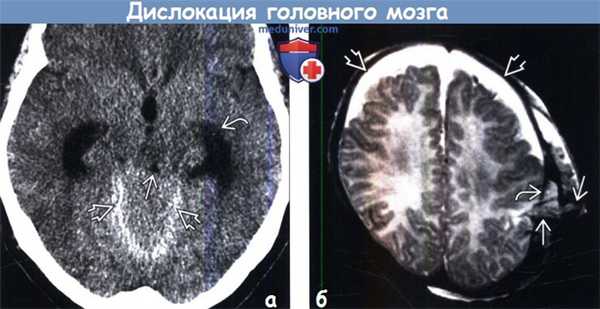

(а) Бес контрастна я КТ, аксиальный срез: признаки восходящего транстенториального вклинения головного мозга. Выявляется смещение червя мозжечка кверху через вырезку его намета с уплощением и компрессией крыши мозга. Также определяется компрессия водопровода, что обусловливает острую гидроцефалию с трансэпендимальным распространением ликвора

(б) МРТ, Т2-ВИ, аксиальный срез: у младенца с переломом левой теменной кости определяется транскраниальное вклинение головного мозга и сосудов сквозь дефект твердой мозговой оболочки. На изображении также определяются хронические СДГ